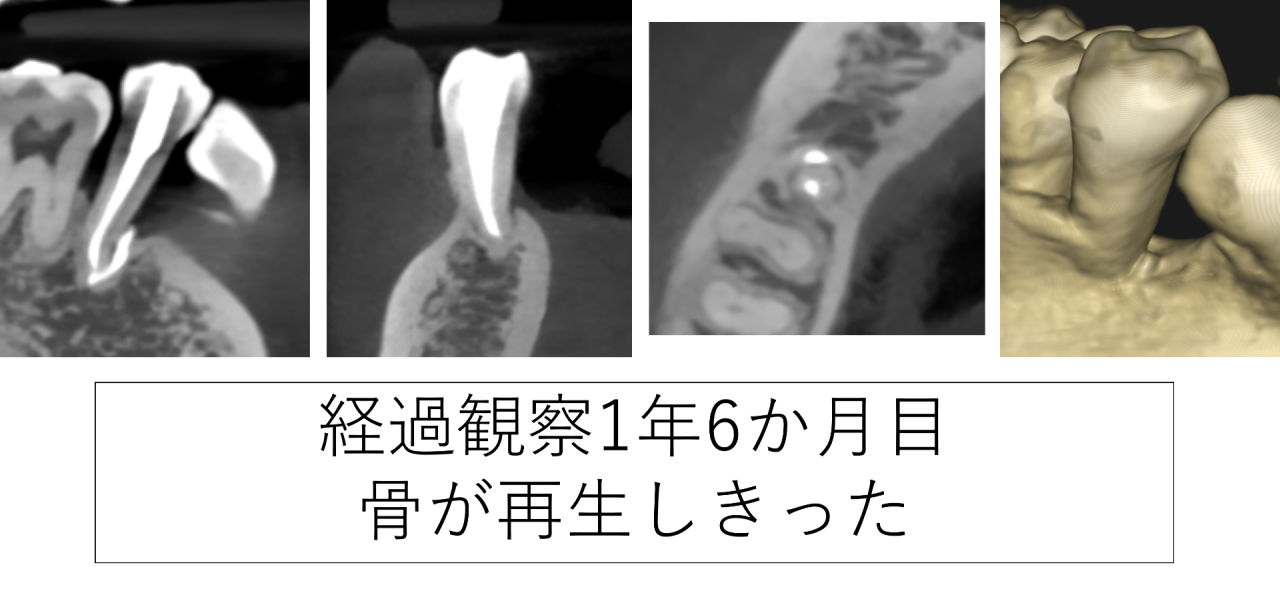

1年6ヶ月後のCTです。骨が再生しました。歯の根が骨に埋まっていることが分かります。骨の再生量としてはこのあたりが限界ですので、隣の歯とのセメント固定は続けて助け合って長持ちさせることにしました。

歯ぐきの検査も3ミリと正常の値になりました。患者様はグラグラ揺れず痛みも腫れも無くなり、とても喜ばれました。本当に良かったです。